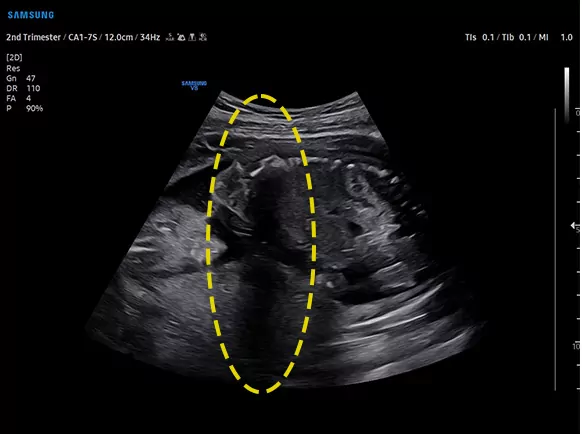

Покращуйте приховані структури в затінених областях

ShadowHDR™ вибірково застосовує високочастотний і низькочастотний ультразвук для виявлення тіньових областей, таких як голова плода або хребет, де відбувається затухання.